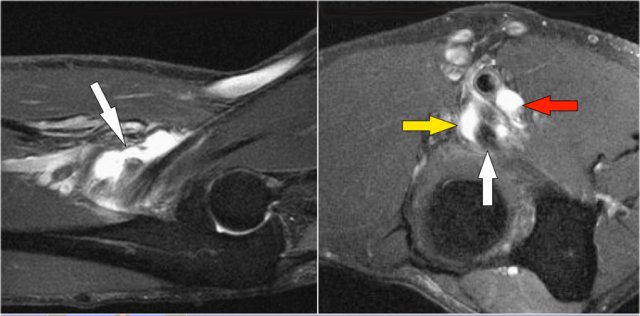

These images are of a patient with anterior elbow pain.

There was no recent injury.

The clinical diagnosis was a biceps tendinitis or a bicipital bursitis.

The findings on the coronal MR-images are quite uncommon.

If you would see this in the capitellum you would call it an osteochondral lesion of the capitellum.

So this is called an osteochondral lesion of the trochlea.

Notice the small cystic changes (white arrow).

There is also a small cartilage defect.

An osteochondral lesion of the trochlea is usually seen in younger patients, who have an immature skeleton.

It is seen in the lateral trochlea like in this case due to repetitive hyperextension in an area with tenuous blood supply.

It is also seen in the medial trochlea due to laxity and posteromedial abutment.

Here a different patient.

Notice that it is a young patient, because the physis is still open.

There is a large osteochondral lesion in the lateral trochlea (yellow arrows).

Notice the edema in the subchondral bone (red arrow).

The cartilage is still intact.